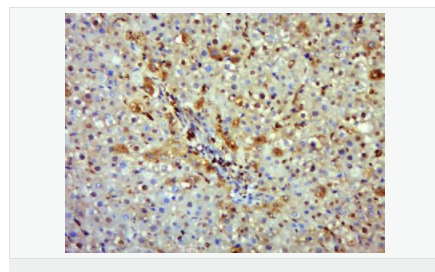

| 產(chǎn)品介紹 | Nitric oxide (NO) is an inorganic, gaseous free radical that carries a variety of messages between cells. Vasorelaxation, neurotransmission and cytotoxicity can all be potentiated through cellular response to NO. NO production is mediated by members of the nitric oxide synthase (NOS) family. NOS catalyzes the oxidization of L-arginine to produce L-citrulline and NO. Two constitutive isoforms, brain or neuronal NOS (b or nNOS, type I) & endothelial cell NOS (eNOS, type III), and one inducible isoform (iNOS, type II), have been cloned. All NOS isoforms contain calmodulin, nicotinamide adenine dinucleotide phosphate (NADPH), flavin adenine dinucleotide (FAD), and flavin mononucleotide (FMN) binding domains. Nitric oxide synthase is expressed in liver, macrophages, hepatocytes, synoviocytes, stimulated glial cells and smooth muscle cells. Cytokines such as interferon-gamma (IFN), tumor necrosis factor (TNF), interleukin-1 and -2, and lipopolysaccarides (LPS) cause an increase in iNOS mRNA, protein, and activity levels. Protein kinase C-stimulating agents exhibit the same effect on iNOS activity. After cytokine induction, iNOS exhibits a delayed activity response which is then followed by a significant increase in NO production over a long period of time. Human iNOS is regulated by calcium/calmodulin (in contrast with mouse NOS2). Function: Produces nitric oxide (NO) which is a messenger molecule with diverse functions throughout the body. In macrophages, NO mediates tumoricidal and bactericidal actions. Also has nitrosylase activity and mediates cysteine S-nitrosylation of cytoplasmic target proteins such COX2. Subunit: Homodimer. Binds SLC9A3R1. Tissue Specificity: Expressed in the liver, retina, bone cells and airway epithelial cells of the lung. Not expressed in the platelets. Similarity: Belongs to the NOS family. Contains 1 FAD-binding FR-type domain. Contains 1 flavodoxin-like domain. SWISS: P35228 Gene ID: 4843 Database links: Entrez Gene: 4843 Human Entrez Gene: 18126 Mouse Omim: 163730 Human SwissProt: P35228 Human SwissProt: P29477 Mouse Unigene: 709191 Human Unigene: 2893 Mouse Unigene: 10400 Rat Important Note: This product as supplied is intended for research use only, not for use in human, therapeutic or diagnostic applications. 合成與降解(Synthesis and Degradation) 催化生物體內(nèi)一氧化氮(NO)生成的酶。分神經(jīng)型一氧化氮合成的酶(nNOS or NOS-1)、誘導(dǎo)型一氧化氮合成的酶(iNOS or NOS-2)、內(nèi)皮型一氧化氮合成的酶(eNOS or NOS-3)。 |